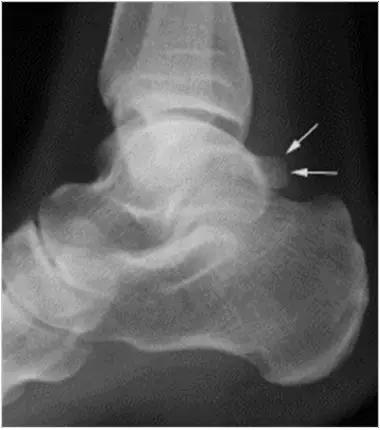

男,11岁,自述后踝下方疼痛,活动时为甚,并有一突起。

- 踝关节正侧位X 线平片,侧位片均显示距骨后方有三角形或椭圆形的距后三角骨。部分病例伴有轻度的踝关节骨性关节病。

- MRI 检查示距后三角骨及周围软组织有水肿信号,距后三角骨和距骨之间正常的低信号纤维连接中断,出现液性信号。